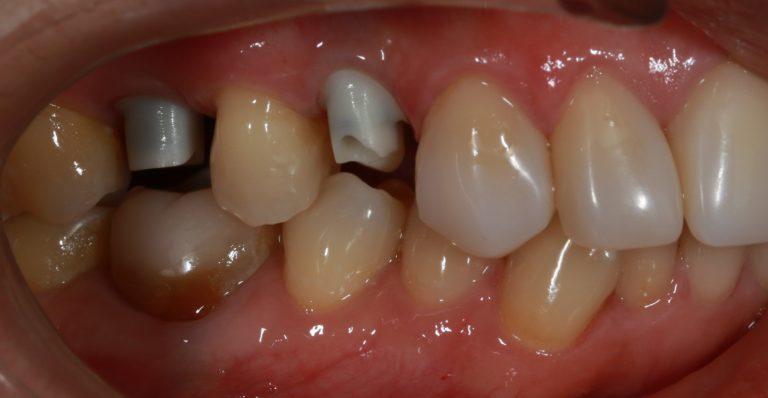

- В случае снижения жевательной функции.

- Когда наблюдаются проблемы с дикцией или изменениями в пропорциях лица из-за отсутствия зубов.